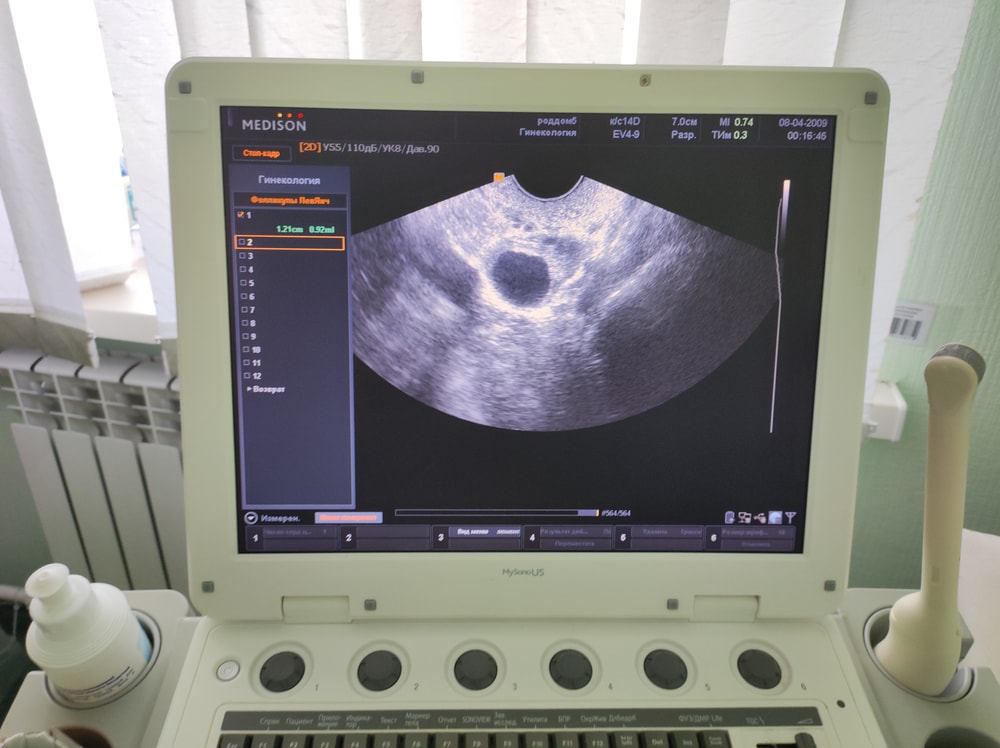

Узи, фолликулометрияДевочки посмотрите пожалуйста по фотографии похоже на фолликул или на жёлтое тело .19 мм .есть свободная жидкость .ещё фотографии есть предыдущая фотография с фолликулометрии

Если жидкость , но фолликул совулировал

Анастасия Абраамян, благодарю вас .как думаете .похоже сегодняшнее фото что образуется жёлтое тело ?

Анастасия Абраамян, благодарю .врач узи сказала или уже была овуляция или вот только будет .может яйцеклетка недавно вышла правильно ?

Светлана , если произошёл разрыв овуляции уже сейчас идет 48 часов